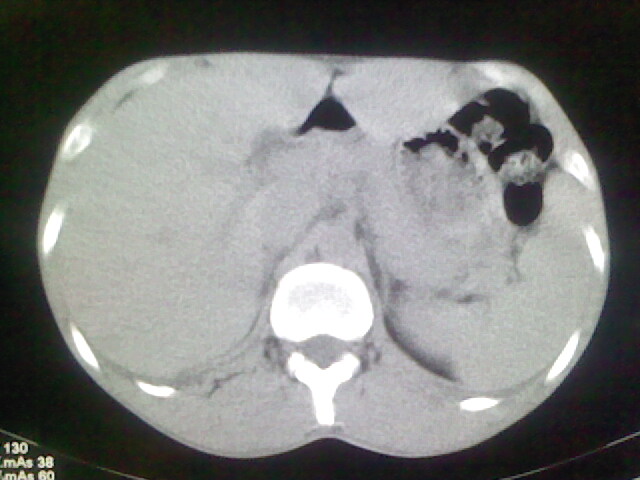

以下是引用杀毒软件在2008-9-3 6:11:00的发言:[br]侵袭性胸腺瘤------一般不侵到气管旁[br][br]考虑----纵隔淋巴瘤,心包及胸膜受累

以下是引用随光逐影在2008-9-3 7:07:00的发言:[br]1)考虑淋巴瘤可能。2)双侧胸腔积液(以左侧为甚)。3)心包积液。